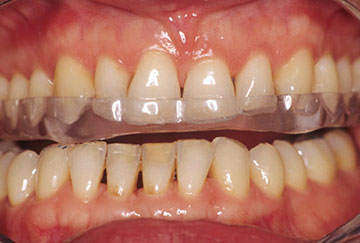

Bruxisme et usure dentaire